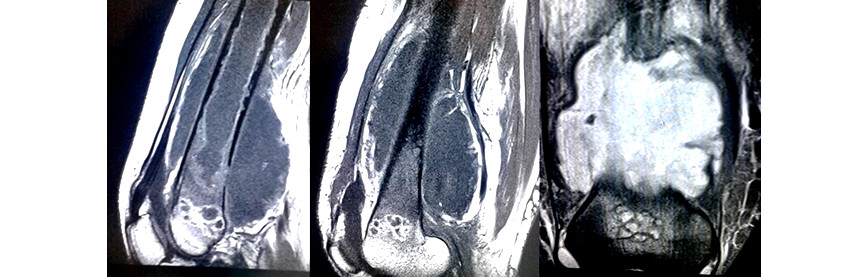

Volver a los detalles del artículo Sarcoma sinovial con invasión medular